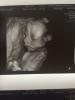

@musel, у вас такие кадры хорошие, и лицо, и ручки и тело👍👶

Фото в 20 недель в Ультрамеде дали это что-то😂😂😂Муж спросил - а где тут лицо? А я сама не знаю😱🙈в 24 недели фото было уже суперским!👍Правда в Семье, и мне кажется у них аппарат лучше все же🤗☝️

Были в ультрамед на Достоевского, все понравилось, только маленькая она ещё, фото пока не очень, да и оно там вроде как бонусом идёт вместе с видео. С сыном в первую беременность фото в 32 недели делали, очень даже похож был)